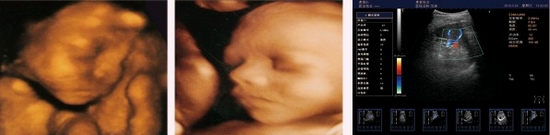

HY6000pro阿凡達(dá)雙屏三維彩色多普勒超聲診斷系統(tǒng)

阿凡達(dá)采用多譜勒超聲成像技術(shù)和高精度數(shù)字波束形成技術(shù),融合組織諧波成像、斑點抑制、多波束并行等先進(jìn)的圖像處理技術(shù)和高效的全數(shù)字圖文管理系統(tǒng)、輕松獲得更清晰的超聲圖像,專業(yè)化的測量軟件包可充分滿足臨床各種定量分析需求,靈活的配置和完全人體工學(xué)設(shè)計,提升了醫(yī)生臨床診斷的信心和臨床檢查的效率。

精確三維(3D)成像系統(tǒng)

全數(shù)字精確三維(3D)成像系統(tǒng),采用探頭陣元切割掃描,采集大量

精確地三維數(shù)據(jù),快速生產(chǎn)高分辨率、高清晰度的精確三維圖像,更

好的進(jìn)一步測量和診斷。

精確血流成像

智能識別血流運動和組織運動,使血流更充盈,組織邊界更清晰。